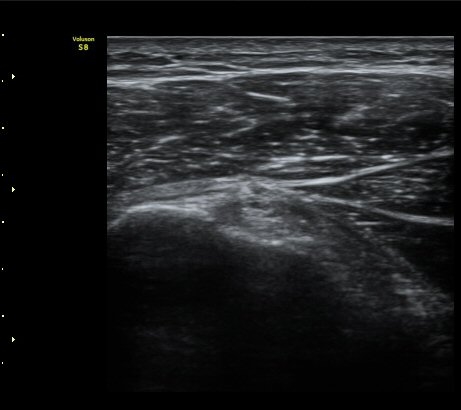

±Ø»ó°Ç Ⱦ´Ü¸é°Ë»ç¿¡¼­ ±Ø»ó°Ç ±ÙÀ§ºÎ¿¡¼­´Â ƯÀÌ ¼Ò°ßÀ» º¸ÀÌÁö ¾ÊÀ¸³ª ±Ø»ó°Ç ¿øÀ§ºÎ¿¡¼­

ÇÇÁú°ñ ¿¬°á ¼Ò½Ç°ú ¹Ì¼¼ÇÑ °ñÆíÀÌ °üÂûµÊ(»çÁø 6, 7).